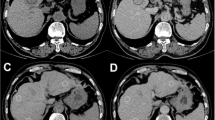

(A–L) Photoacoustic imaging with pretreatment (on day 8) and posttreatment (on day 13) hemoglobin map and oxygen saturation map in animals treated with ECT and i.v. (A–D), i.t. (E–H), or i.v. + i.t. (I–L) administration of BLM. In the oxygen saturation map, the lowest saturation is dark blue, whereas the highest levels are red. Black lines indicate the tumor outline. Scale bars: 1 mm. M–N) HbT and SO2 were measured in the whole tumor area. Data are given as mean ± SEM; *p < 0.05 vs. SO2 pretreatment in each group; #p < 0.05 vs. SO2 posttreatment in i.t. group.

HbT and SO2 were additionally assessed five days following the ECT procedure (day 13), whereas the tumor volume could not be exactly measured anymore due to edema formation. The i.v. + i.t. group demonstrated the largest reduction in HbT (13.1%) compared to pretreatment values, whereas in the i.v. and i.t. groups the reduction in HbT was lower with 12.0 and 8.0%, respectively (Fig. 1). Despite the reduction in HbT of the tumor tissue in all groups after ECT, the comparison of pre- and posttreatment values revealed no significant differences after treatment in each group. Furthermore, the analysis of the posttreatment HbT levels revealed no significant differences among the groups.

The i.v. and the i.t. group exhibited a 44.0 and 35.2% reduction in SO2 of the tumor area compared to pretreatment values, respectively. The largest reduction in SO2 was detected in the i.v. + i.t. group with 46.6%. Finally, the comparison of posttreatment oxygenation levels among the groups revealed a significantly reduced SO2 after i.v. (40.1%) and i.v. + i.t. (42.7%) injection when compared to the i.t. treatment (48.8%) on day 13 (Fig. 1).